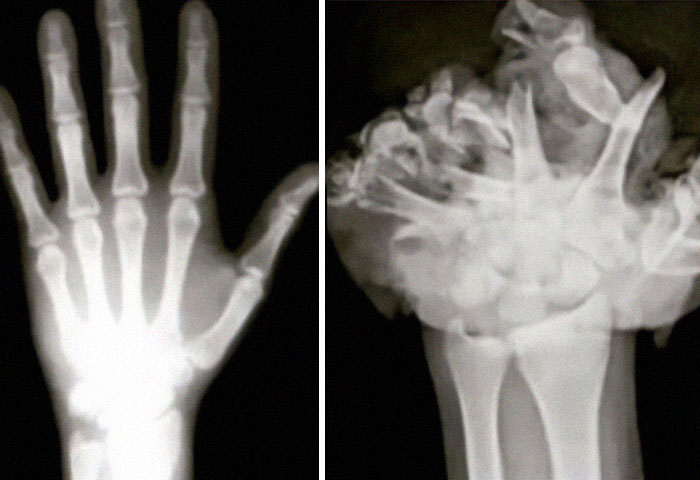

Antes y después de una operación de duplicación craneofacial